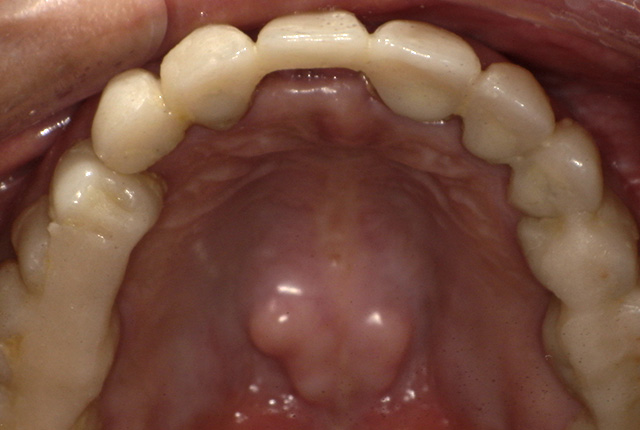

| 主訴 | 噛めない、食事がしっかりできる様になりたい。 |

| 診査診断 | 歯周病、歯の崩壊、不良補綴。 全顎的咬合異常、前歯の噛み合わせ、奥歯の噛み合わせに問題あり。 |

| 治療計画 | 欠損部インプラント 不良補綴のやり直しと欠損部インプラント。 咬合の再構築、なるべく歯を残せる様に治療計画を立案。 |

| 治療期間 | 6ヶ月 |

| 費用 | 290万円 |

| リスク | 一般的なインプラントのリスク、抜歯のリスク |